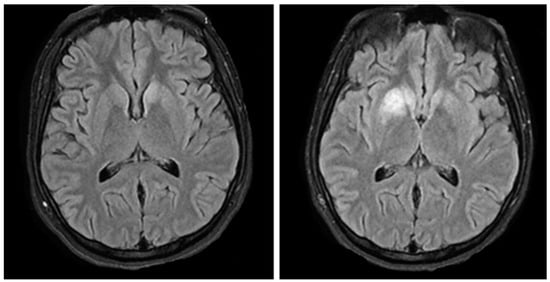

A 21-year-old gravida 2, para 1001 woman at 20 weeks’ gestation presented to labor and delivery for increased seizure activity in addition to frequent falls, loss of consciousness, and concern for trauma to the abdomen in the setting of pregnancy. Prior to this exacerbation of symptoms, she had a four-month history of similar, though less frequent, episodes. Her previous neurologic workup one month prior revealed a 72 h electroencephalography (EEG) with epileptic seizures of the left frontotemporal region, but a normal magnetic resonance image of her head (Figure 1). She had been started on levetiracetam, 1500 mg twice daily.

Figure 1.

(Left) Patient’s head MRI two months before. (Right) Patient’s head MRI upon hospital admission.

A computed tomography (CT) without contrast of the patient’s head was performed which showed asymmetric hypoattenuation of the right basal ganglia concerning for possible infarction secondary to venous thrombosis or inflammatory changes. The MRI of her head was significant for bilateral T2 hyperintensities in the mesial temporal lobes extending to the basal ganglia, some of which showed restricted diffusion (Figure 1). Head magnetic resonance imaging of the arteries (MRA) and veins (MRV) was negative.

Based on the patient’s initial presentation and imaging, there was concern for a venous versus arterial stroke. Her bilateral basal ganglia edema, restricted diffusion in the right basal ganglia, and bilateral T2 hippocampi hyperintensities represented a significant change from her previous imaging two months prior; however, arterial versus venous infarct was deemed less likely given her lack of headache and encephalopathy. In addition, the MRA and MRV studies showed no evidence of thrombosis. In 2016, a reported case of a 45-year-old woman diagnosed with anti-LGI1 encephalitis who presented with a cryptogenic ischemic stroke was published by McGinley et al. []. The authors discuss the possibility of autoimmune encephalitis being a possible risk factor for ischemic stroke. It was hypothesized that systemic inflammation during autoimmune encephalitis leads to a prothrombotic state that can ultimately lead to a stroke, versus autoimmune encephalitis causing an upregulation of other antibodies that mediate vascular damage. It is unclear if autoimmune encephalitis increases the risk of ischemic stroke; however, our case shows no evidence of ischemic stroke, and this diagnosis was ruled out []. The patient’s MRI changes were likely secondary to limbic encephalitis and associated uncontrolled seizures.